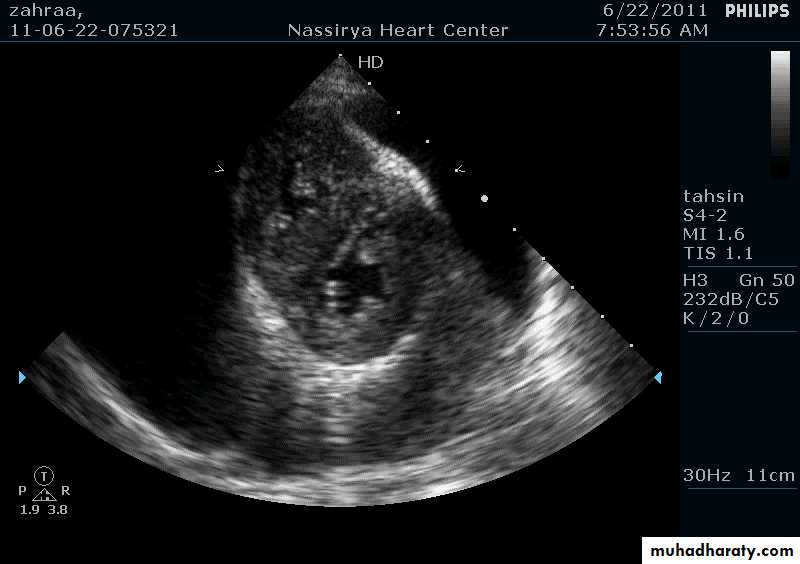

Pericardial Effusion: Investigation

Echocardiography: establishes the diagnosis31

40Cardiac tamponade

Acute cardiac failure caused by compression of the heart by large or rapidly expanding pericardial effusion41

Echocardiography & Doppler:

Establish the diagnosis44